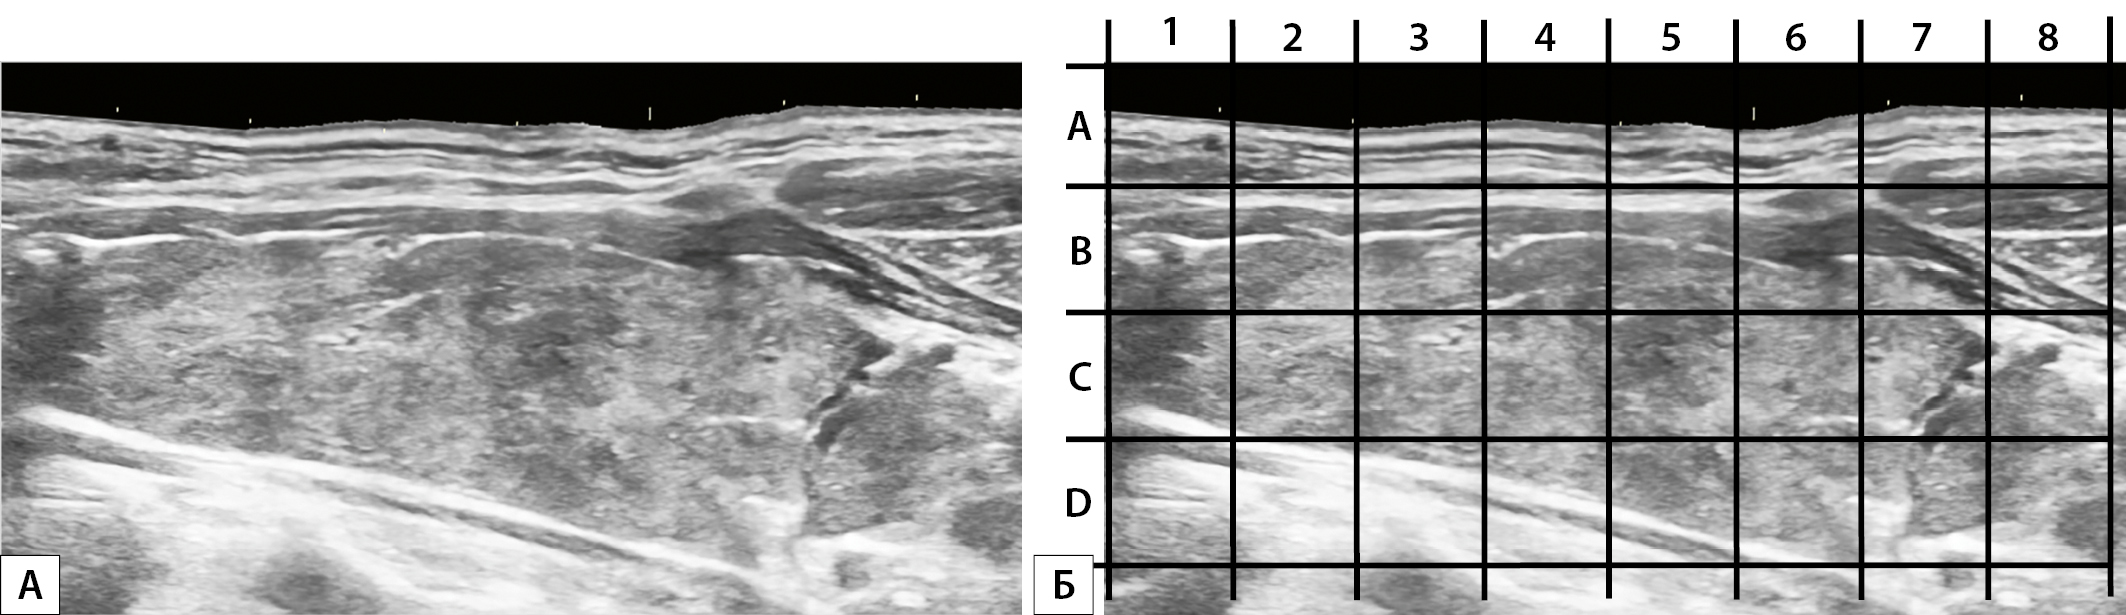

1. Рисунок 1. 1А. Эхограммы щитовидной железы в парасагиттальной плоскости. 1Б. Та же эхограмма с нанесенной сеткой, предназначенная для количественной оценки площади локального понижения эхогенности